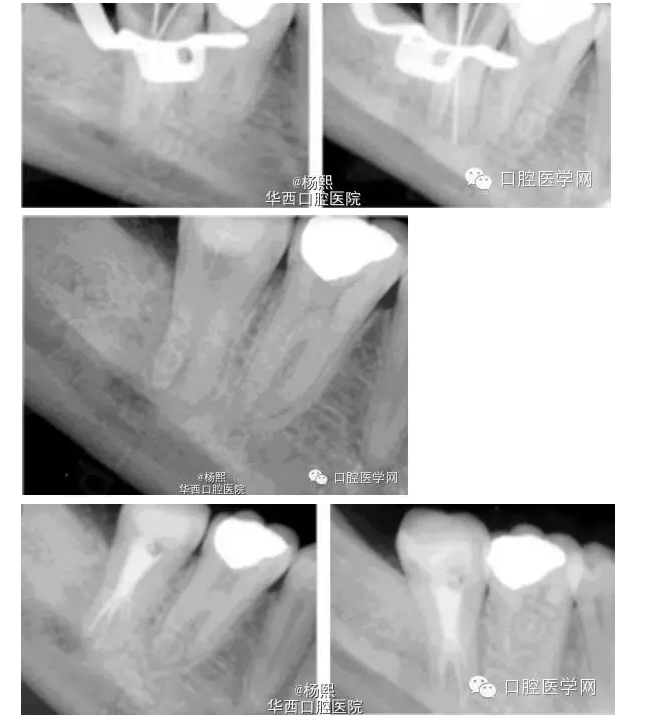

處理:初診-去除銀汞充填物后常規(guī)擴挫,然后封藥。

復(fù)診:根管充填+修復(fù)

隨訪:18月后隨訪X線片示根尖周暗影消失。